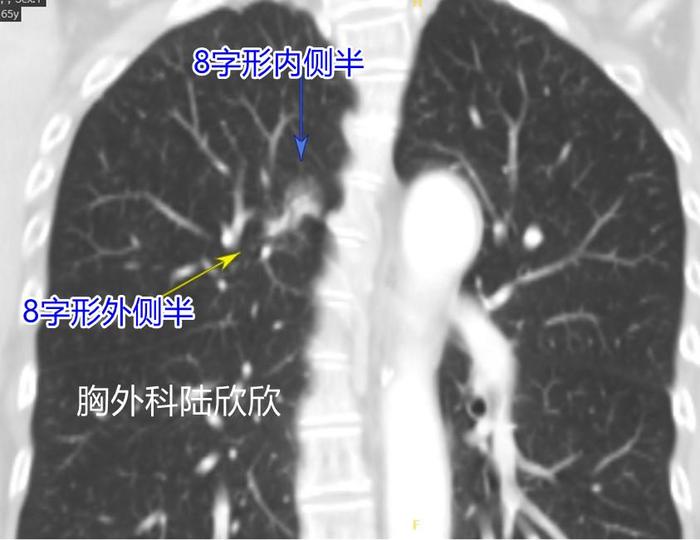

上图,为冠状位的CT第29层面,可见这个磨玻璃结节形状为8字形,内侧半和外侧半通过一个细桥相连。这张图显示结节的8字的形状最好。

上图,为冠状位的CT第28层面,可见这个磨玻璃结节形状为接近8字形,最大径是27毫米比横断面上的15毫米要大的多